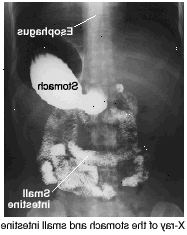

Μια ανώτερη σειρά GI είναι μια εξέταση ακτινογραφία του ανώτερου πεπτικού συστήματος (η περιοχή από το στόμα σας για την έναρξη του λεπτού εντέρου σας). Η δοκιμή αυτή βοηθά το γιατρό σας να βρείτε οποιαδήποτε προβλήματα, όπως έλκος, όγκοι, και ορισμένες ασθένειες. Υπάρχει μια μικρή ποσότητα της ακτινοβολίας με μια ανώτερη σειρά GI. Ωστόσο, τα οφέλη της δοκιμής αυτής υπερβαίνουν κατά πολύ τυχόν κινδύνους.

Θα σας ζητηθεί να πιείτε βάριο (ένα υγρό που ενισχύει τις εικόνες x-ray). Μπορείτε επίσης να καταπιούν "fizzies", μια ουσία που κάνει αέρα συσσωρεύονται στο στομάχι σας. Μην ρέψιμο, ακόμα κι αν αισθάνεστε ότι πρέπει να. Για τις καλύτερες εικόνες, ίσως χρειαστεί να σταθεί ή να βρίσκονται σε διαφορετικές θέσεις. Όταν έρθει η ώρα να αναλάβει τις ακτινογραφίες, θα σας ζητηθεί να κρατάτε την αναπνοή σας για μια στιγμή. Μπορεί να χρειαστεί να περιμένετε λίγο μετά τη δοκιμή για να βεβαιωθείτε ότι οι εικόνες είναι αναγνώσιμα.